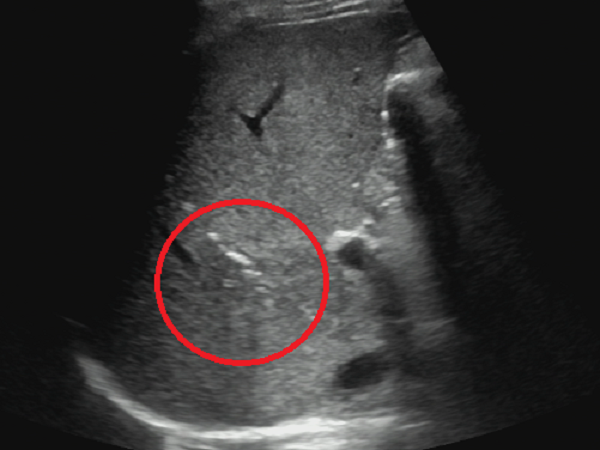

超声所见:肝多发脓肿,其中已完全液化较大者位于右肝前叶上段(图1),故拟行经皮右肝前叶上段脓肿穿刺置管引流术。

图1 红色圆圈处为肝脓肿